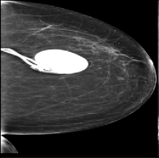

The 136 true outliers are classified into seven categories by the professional radiologist: implant, pacemaker, cardiac loop recorder, improper radiography, atypical lesion/calcification, incorrect exposure parameter and improper placement. It is worth noting that, despite the fact that mammograms with implants were eliminated during the preprocessing step (see Section 2.6), there were still mammograms with implants remaining since they were incorrectly categorised as having no implants. Figure 1 depicts representative outliers for each category, and Table. 4 displays the number and percentage of outliers in each category given that that the total number of true outliers is 136.

Figure 1: Examples of true outlier subgroups in the ADMANI dataset. From left to right and top to bottom, the outlier types are: implant, pacemaker, cardiac loop recorder, improper radiography, improper radiography, atypical lesions/calcification, incorrect exposure parameter, improper placement. Improper radiography is classified into two subtypes: those with heterogeneous pectoral muscle and the rest, respectively.